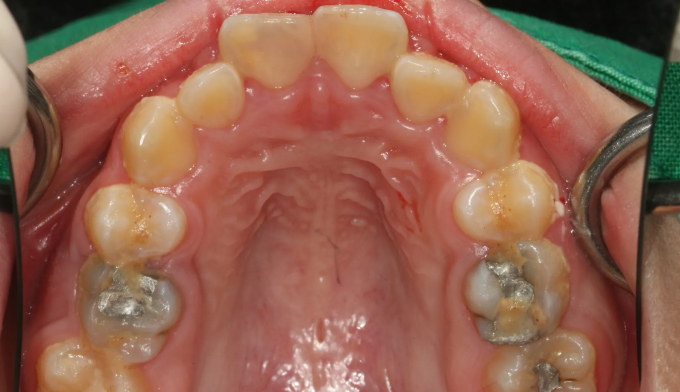

After

발치없이 윗니를 전체적으로 후방이동시켜서 돌출입을 해소하였고, 가지런하지 못한 치열을 모두 배열하였습니다.